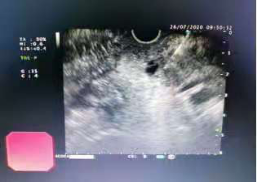

消化内科内镜中心目前是渭南市占地面积配套设施最齐全的内镜中心,达到了省级先进水平,能够满足各种胃肠检查治疗技术。每年进行胃肠镜检查15000余例,各种治疗2千余例,进行常规胃肠镜下治疗外可以进行 食道异物取出、食道及结肠狭窄扩张及支架置入、食道静脉曲张套扎、胃底静脉硬化剂注射、胃底曲张静脉组织胶注射、胆道ERCP检查,胆道支架,胆道结石取出、超声内镜检查(EUS)、胃肠粘膜下病变剥离术(ESD)等,其中 “三E”技术均达到了省内先进技术,填补了渭南地区在心血管领域的多项空白。急诊内镜下治疗上消化道出血达到了省内先进水平。科室重视科研,目前有两项独立完成的市级科技新项目,同时与省级单位联合两项省级课题,近3年完成省级以上论文40篇,其中两篇SCI文章。科室是渭南市消化内镜质控中心、渭南市消化内科专业委员会主委单位、渭南市消化内镜专业委员会主委单位、担负渭南地区消化及消化内镜专业学术的发展。